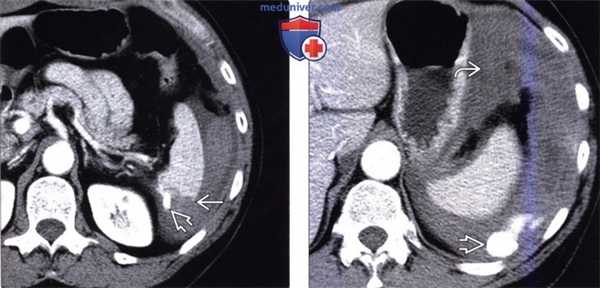

(Слева) На аксиальной КТ с контрастным усилением определяется глубокий разрыв селезенки и активная экстравазация. Обратите внимание на разрыв нижнего полюса селезенки, где обнаруживается участок высокой плотности, свидетельствующий об артериальной экстравазации.

(Справа) На аксиальной КТ с контрастом у этой же пациентки определяется большая гематома около селезенки, а также признаки интенсивной артериальной экстравазации.